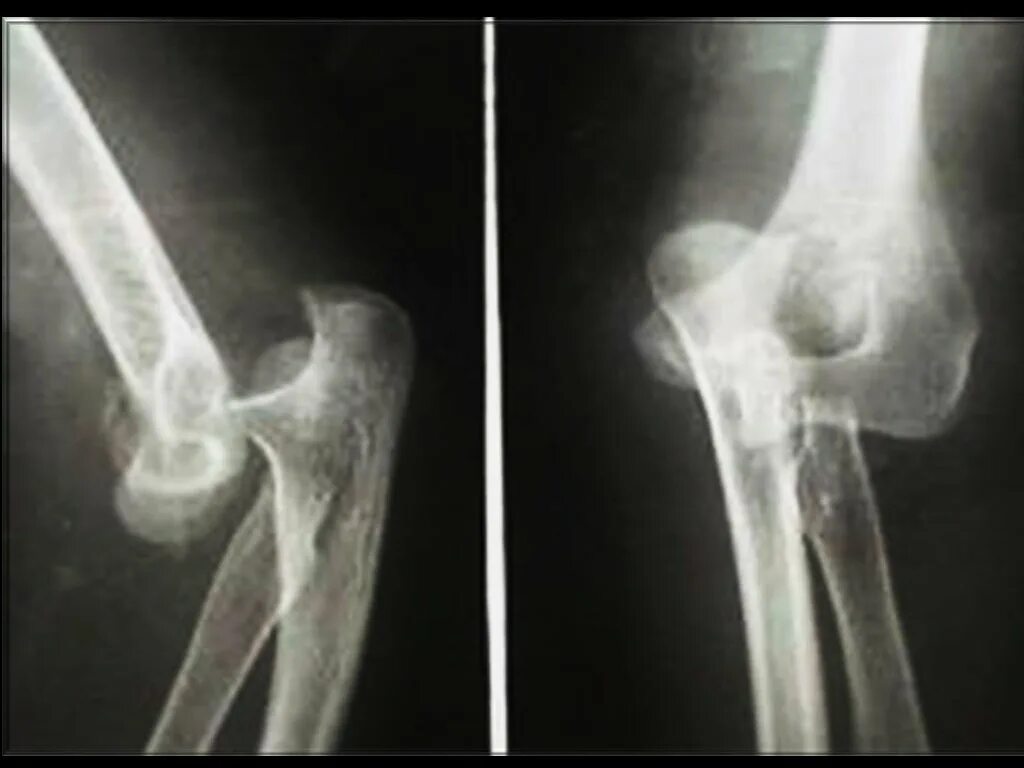

Подвывих локтевого сустава у ребенка